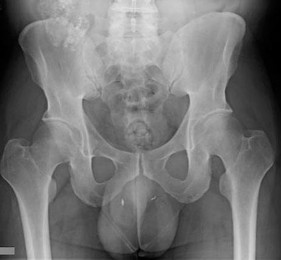

A 13-year-old obese male presents with left hip pain and an obligatory external rotation of the left hip when it is passively flexed. Radiographs confirm a severe left slipped capital femoral epiphysis (SCFE).

Which of the following patient characteristics is an absolute indication for prophylactic pinning of the contralateral asymptomatic right hip?

Explanation

Prophylactic pinning of the contralateral asymptomatic hip in a patient with a unilateral SCFE is controversial for standard cases, but it is unequivocally recommended for patients with underlying endocrine disorders (such as hypothyroidism, panhypopituitarism, and renal osteodystrophy). These patients have an exceptionally high incidence of bilateral involvement. Other factors like young age (<10 years) or open triradiate cartilage may also sway a surgeon toward prophylactic pinning.